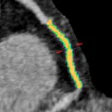

T1 mapping speeds myocardial assessment in cardiac MR